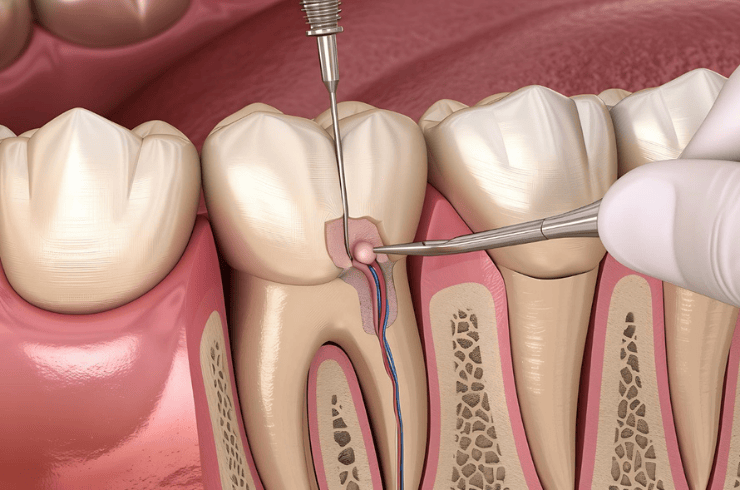

Pain-relieving treatment to save infected teeth and prevent extraction.